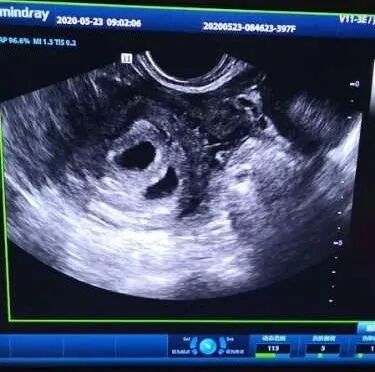

近日,高女士来医院做彩超检查,促排卵成功终怀孕了。通过彩超可以清晰的确定高女士怀孕的事实,看到彩超里期盼已久的孩子,高女士激动地说:“我真的不敢相信,我和家人都觉得是个“奇迹”,感谢蓝湾,感谢朱院长!”